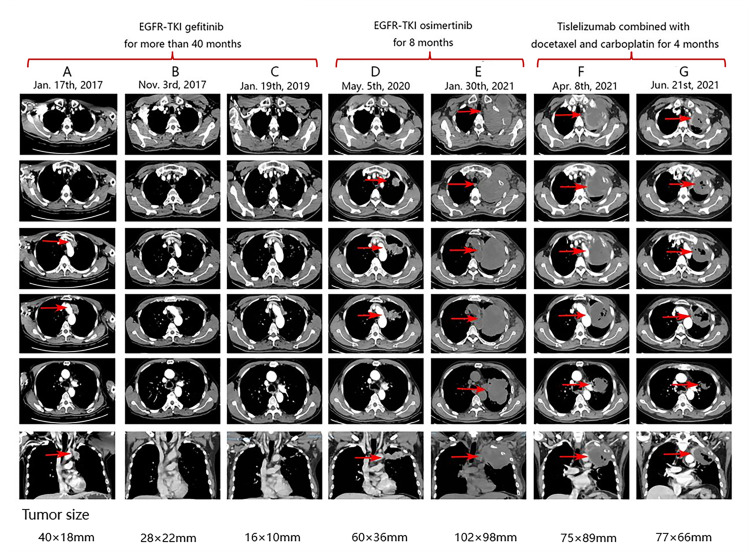

Lung adenocarcinoma (ADC) harboring epidermal growth factor receptor (EGFR) mutations rarely transforms into squamous cell carcinoma (SCC) following resistance to targeted therapy. Here, we present a case of EGFR-positive ADC that transformed into EGFR-negative SCC after developing resistance to EGFR tyrosine kinase inhibitors (TKIs). The patient experienced progressive disease after one cycle of chemotherapy and subsequently underwent five courses of tislelizumab combined with chemotherapy. Although the primary tumor showed a partial response to this combined regimen, intracranial metastases continued to progress, ultimately leading to the patient's death. Notably, the patient survived for 8 months after SCC transformation with immuno-chemotherapy, a significantly longer duration than the previously reported median survival of 3.5 months. This case underscores the occurrence of genomic instability, histological transformation, and dissociated response (DR) following treatment with EGFR-TKIs in EGFR-positive lung ADC. We hypothesize that these phenomena may be driven by tumor heterogeneity and the dynamic variability within the tumor microenvironment (TME).